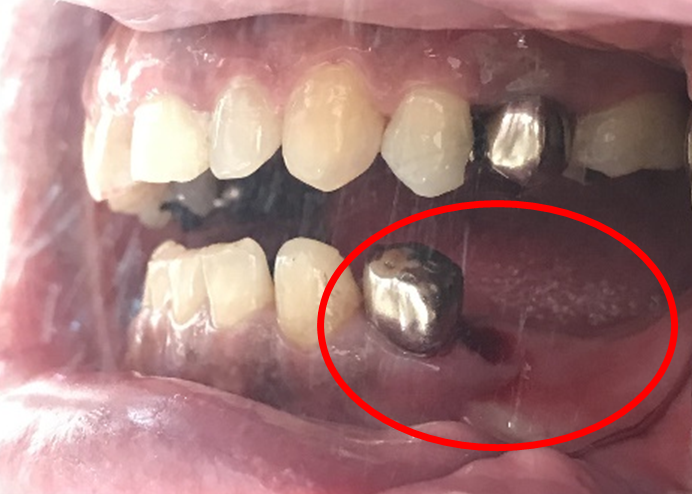

Before

歯根が真っ二つに割れていました

抜いた歯

【抜歯後】